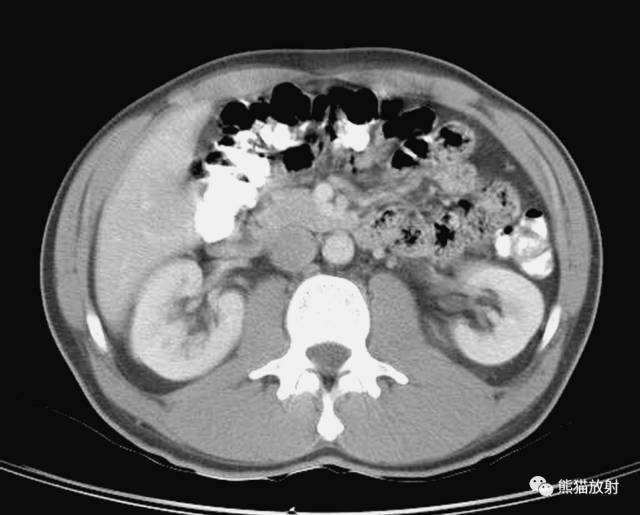

第七层

1、肝脏;2、右肾静脉;3、下腔静脉;4、胆囊;5、结肠右曲;6、十二指肠;7、胰十二指肠下动脉及静脉;8、肠系膜上动脉及静脉;9、左肾静脉;10、肠系膜下静脉;11、横结肠;12、腹直肌;13、空肠;14、内斜肌;15、降结肠;16、腹外斜肌;17、右肾;18、肾锥体;19、髂肋肌(胸段);20、右肾动脉;21、腰方肌;22、腰大肌;23、膈肌;24、椎管;25、棘肌;26、胸椎;27、腰升静脉;28、最长肌;29、腹主动脉;30、左肾动脉;31、肾窦;32、肾盏;33、背阔肌;34、肝肾隐窝;35、肋间淋巴结;36、十二指肠下隐窝;37、腰淋巴结;38、大网膜;39、肾筋膜;40、左侧肠系膜结肠沟;41、左结肠旁沟。